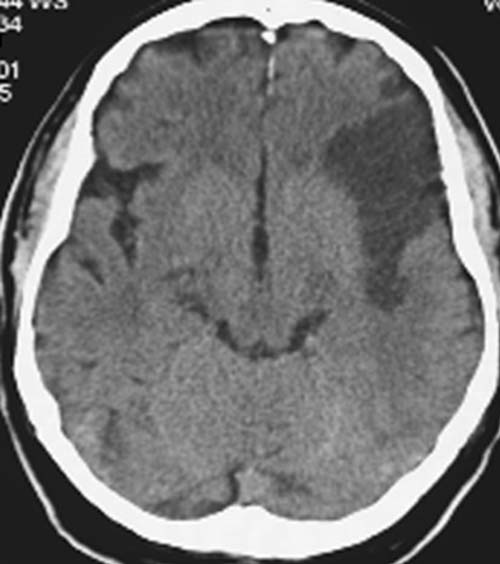

CCT nativ (ohne Kontrastmittel).

Hypodense

Darstellung des vorderen Mediastromgebietes links. Rindenmarkgrenze

links nicht mehr erkennbar.

Subakuter

Mediainfarkt links (48-96h). Da die Stammganglien und ein Teil des

Mediastromgebietes intakt sind, liegt der Mediaverschluss distal nach Abgang

der lenticulostriären Äste im Bereich der Mediatrifurkation.